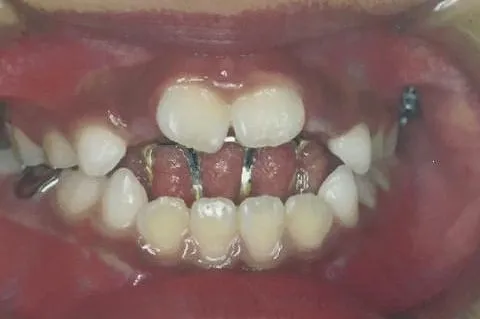

ブラケット矯正

歯の表側にブラケットを付け、そこに金属のワイヤーを通して歯を動かしていく装置です。様々なタイプの不正咬合に対応することができるほか、他の装置よりも費用を抑えることが可能です。